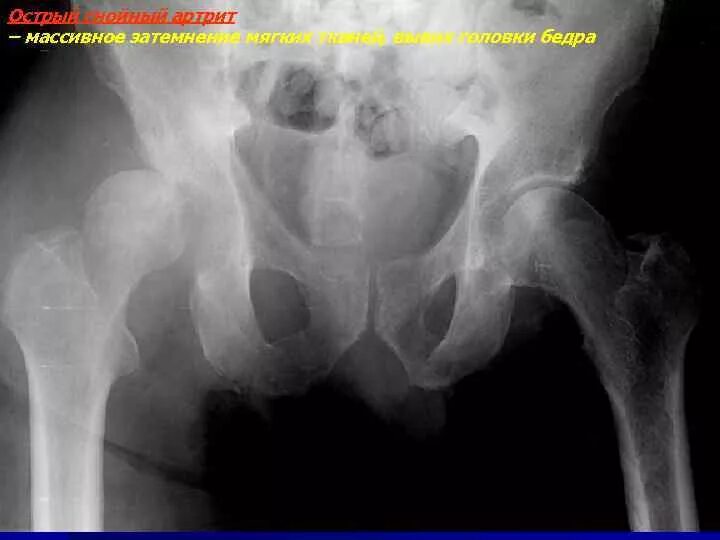

Артрит тазобедренного сустава симптомы